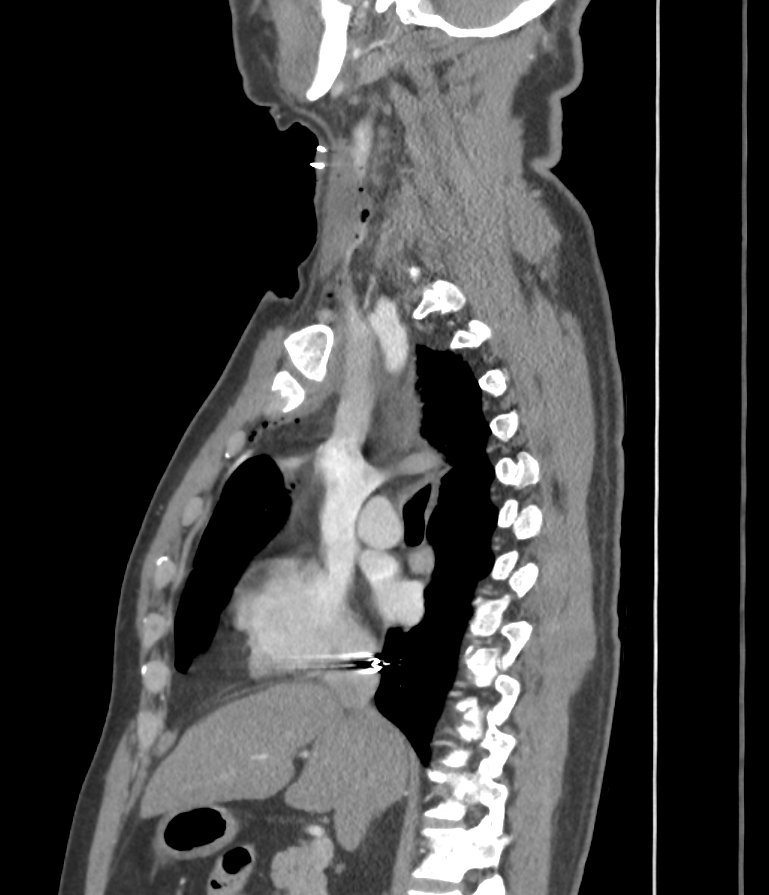

CT Neck showed metallic foreign body piercing the right sternocleidomastoid muscle at the level of lower border of C6 vertebral body, likely abutting the carotid sheath at the level of lower border of cricoid cartilage on right side of neck. Soft tissue density anterior to IJV and CCA -likely haematoma

A CT Thorax was done which showed the metallic pellet migrated through internal jugular vein into inferior

venacava atrial junction.